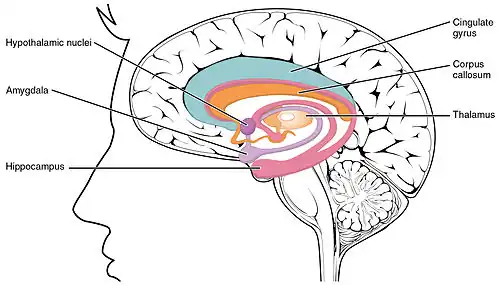

In the limbic system

The hippocampus is one of the structures of the limbic lobe, first described by Broca in 1878, as the cortical areas that line the deep edge of the cerebral cortex.[13] The limbic lobe is the main component of the limbic system.[14] The cingulate gyrus, and the parahippocampal gyrus are the two main parts of the described lobe, which had been largely associated with olfaction.[13] Many studies later culminating in work by Papez, and MacLean, the involvement of other interacting brain regions associated with emotion was recognized.[14] The hippocampus is anatomically connected to parts of the brain that are involved with emotional behavior, including the septal area, the hypothalamic mammillary bodies, and the anterior nuclear complex in the thalamus. MacLean proposed that the associated structures of the limbic lobe be included in what he termed as the limbic system.[14]